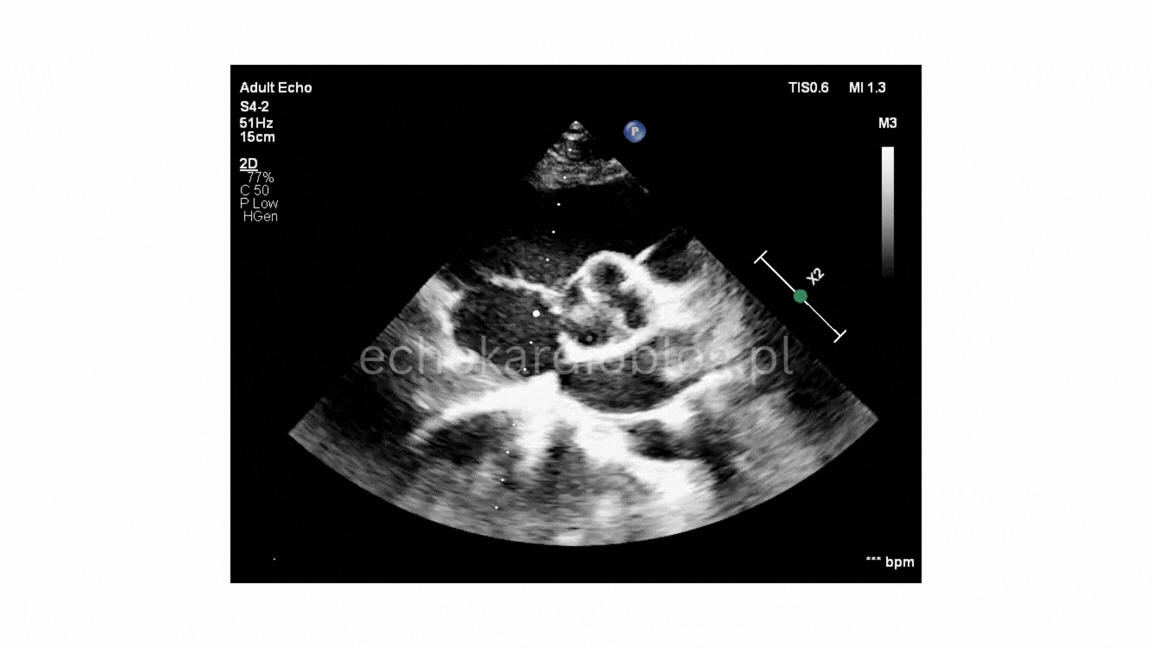

Przypadek 2.A

W pierwszym filmie obraz jest doskonały i budowa zastawki jest oczywista. W drugim – rozpoznanie wymaga większej uwagi i doświadczenia.

In the first video, the image quality is excellent, and the bicuspid morphology is obvious. In the second one, the diagnosis requires more attention and experience.